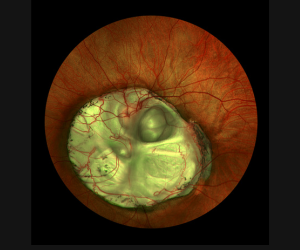

• 1st Place – Fundus Photography Ultrawide Field

california_coloboma_uwf

Coloboma